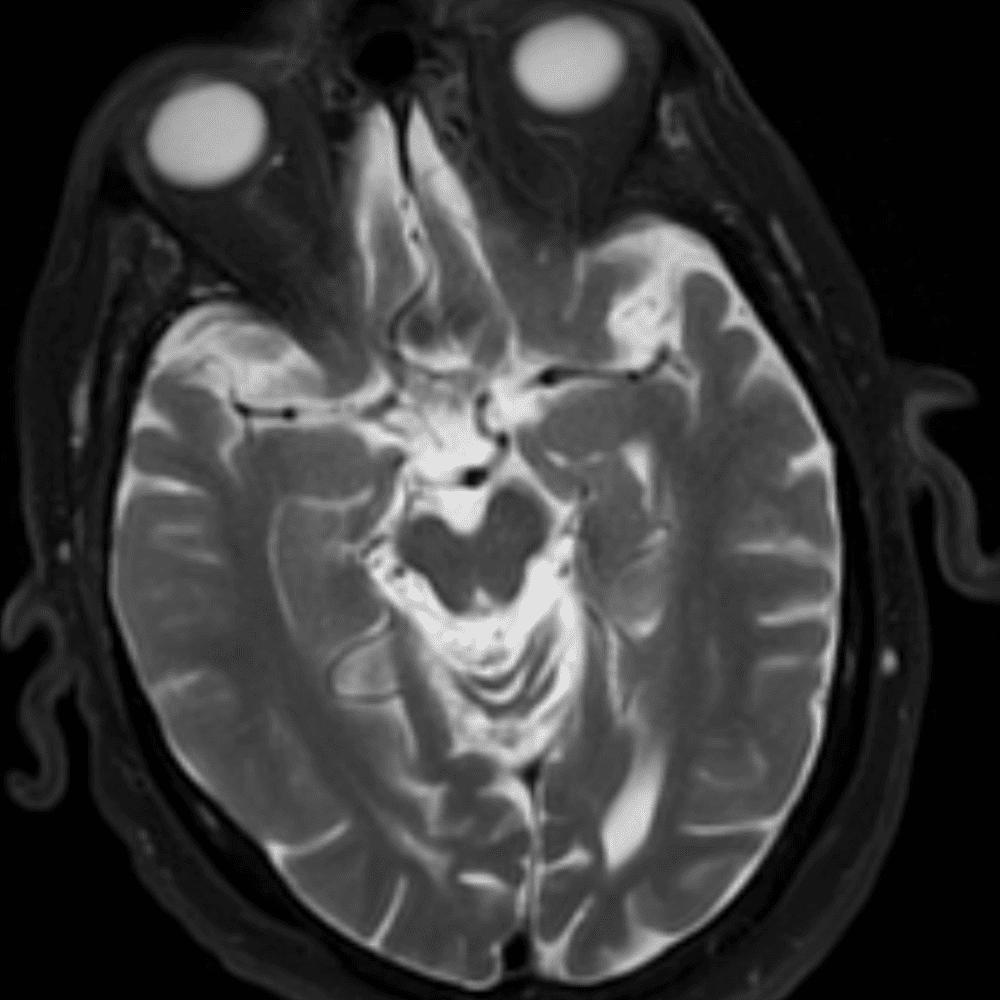

๋‹น์ง ์‹œ ํ”ํžˆ ๋ณผ ์ˆ˜ ์žˆ๋Š” ์‚ฌ๋ก€์˜ ์ „ํ˜•์ ์ธ ์˜ˆ๋ฅผ ํฌํ•จํ•ฉ๋‹ˆ๋‹ค.

39 ์‚ฌ๋ก€

์—ฐ์Šต

๋ฏธ๋ฌ˜ํ•˜๊ฑฐ๋‚˜ ์–ด๋ ค์šด ์‚ฌ๋ก€์™€ ์ผ๋ถ€ ์ •์ƒ ์‚ฌ๋ก€๋ฅผ ํฌํ•จํ•˜์—ฌ ๋‹น์ง์„ ์‹œ๋ฎฌ๋ ˆ์ด์…˜ํ•ฉ๋‹ˆ๋‹ค.

50 ์‚ฌ๋ก€